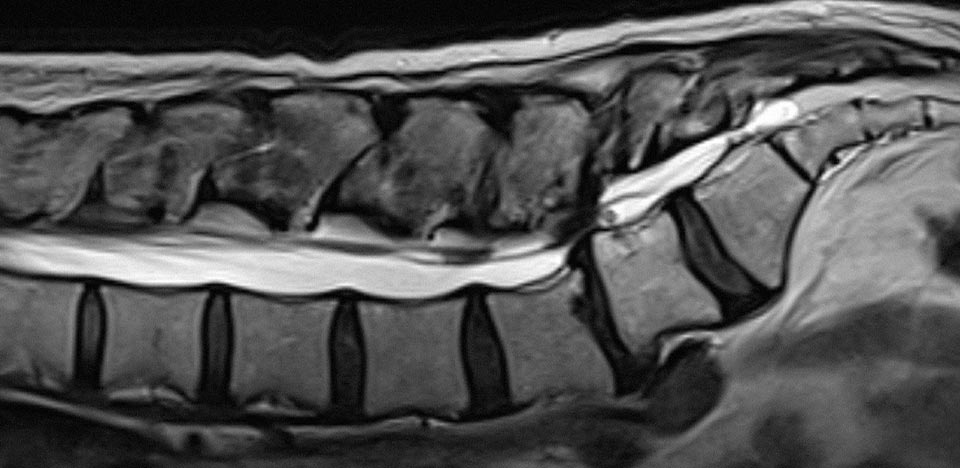

경기동물의료원 뇌신경수술센터는 반려동물의 뇌·척수·말초신경계 이상에 대한 정밀 진단과 고난도 수술을 전문적으로 시행하는 신경외과 특화 센터입니다. CT·MRI·신경학적 검사·내과협진 시스템을 기반으로 발작, 마비, 보행장애 등 중추신경계 질환을 체계적으로 진단하고 수술적 치료를 시행합니다.

• 디스크는 척추 사이의 충격 완충 역할을 하는 구조가 파열되거나 탈출해 신경을 압박하는 질환입니다.

• 통증, 보행 장애, 마비 등이 빠르게 진행할 수 있어 조기 진단과 적절한 치료가 매우 중요합니다.

• 심한 압박이 확인되면 수술로 신경을 감압해 기능 회복을 돕고, 재발 가능성을 줄일 수 있습니다.

• 1.5T MRI, 128ch CT, 척수조영술 등 고도 영상진단 장비 완비

디스크 감압술 (Hemilaminectomy, Pediculectomy)